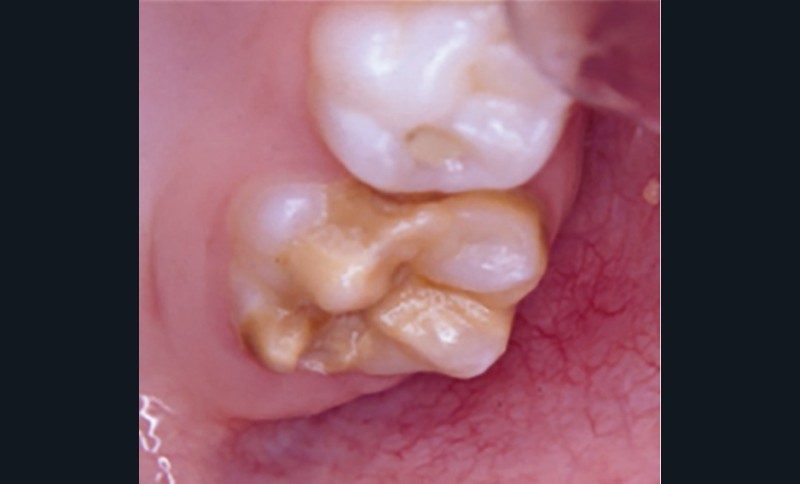

Cliniquement, les dents présentent des colorations blanches ou brunes opaques sur une partie ou sur toute la surface de la dent. Cette atteinte peut être légère (émail blanc, opaque), modérée (coloration jaune, brune, surface crayeuse et effondrement postéruptif de l’email) ou sévère (atteintes associées à des pertes de substances importantes) (fig. 1)

.